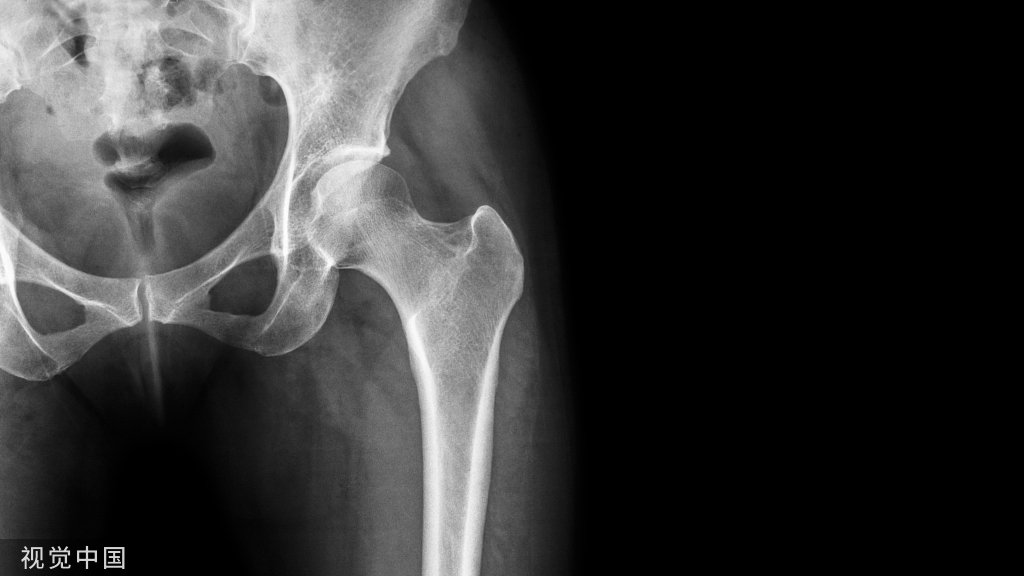

得了骨质疏松吃啥药?母亲的健康你来守护!